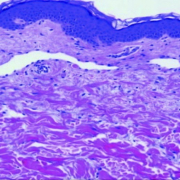

Histologic picture from ACS journal article titled Inflammatory Breast Cancer: The Disease, the Biology, the Treatment https://acsjournals.onlinelibrary.wiley.com/doi/full/10.3322/caac.20082